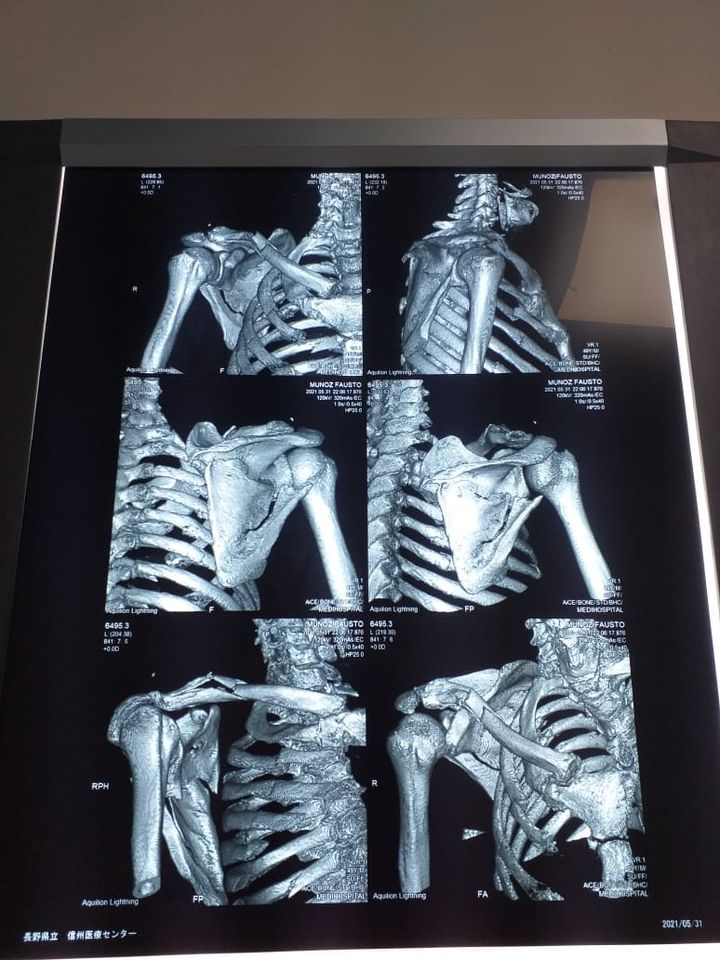

Tras el golpe, producto de la embestida, el chofer se baja del vehículo, lo ve tendido en la calzada y huye del sitio. Rodrigo Muñoz presenta su omóplato destrozado, la clavícula y 12 costillas rotas, así como hay problemas en el pulmón con posible sangre.